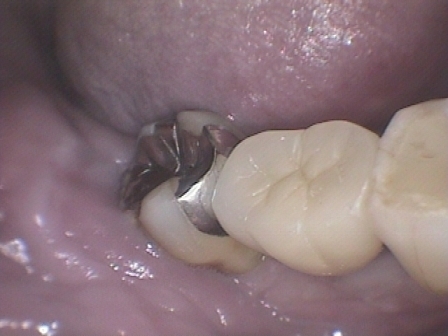

症例2

右下 6 番単独欠損ですが、中等度歯周病(水平的骨吸収あり)のため、ブリッジでの治療ですと隣接歯の寿命を極端に縮めてしまう可能性があります。